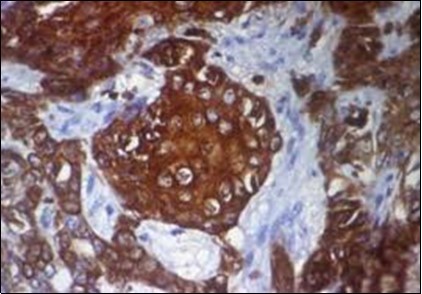

Granular arrangement of malignant cells and intercellular bridges are conspicuous with the demonstration of nuclear atypia, pleomorphism, prominent mitosis and tumour necrosis. A peripheral palisade is discernible within the cellular aggregates. Mitotic figures are common and can be quantified as up to 12 mitosis/ high power field. Tumour differentiation can prominently be of the ductal category with the demonstration of intra-cytoplasmic lumina. Comedo type tumour necrosis is evident along with foci of squamous differentiation The neoplasm is reactive to periodic acid Schiff ‘s (PAS) stain. (Figure 1, Figure 2, Figure 3, Figure 4, Figure 5, Figure 6, Figure 7, Figure 8, Figure 9, Figure 10, Figure 11, Figure 12, Figure 13.

Figure 5.Sweat glandular articulations and malignant cellular aggregates with cystic spaces in eccrine porocarcinoma(17).